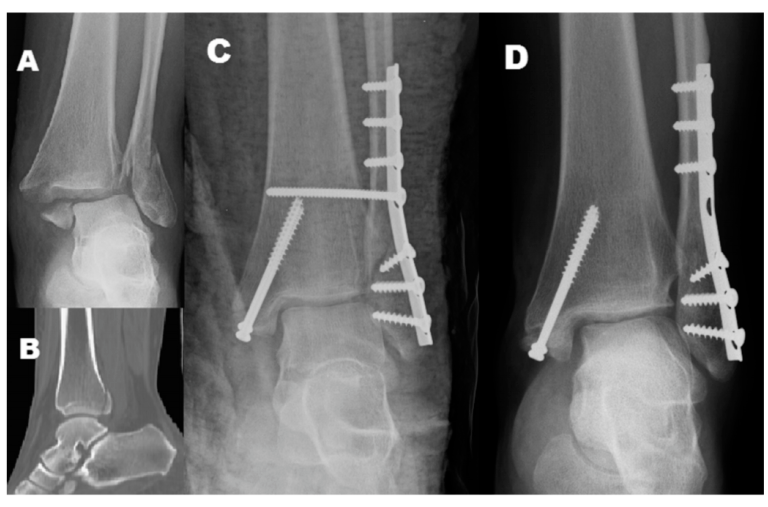

如何预测Danis-Weber B型踝关节骨折下胫腓联合损伤?

Lauge-Hansen分型与Danis-Webe分型为最常见的踝关节骨折分型,在对下胫腓韧带损伤的指导意义上,旋后外旋II°骨折通常认为合并下胫腓前韧带的损伤,下胫腓联合趋于稳定,可能无需下胫腓联合螺钉固定。而Danis-Weber B型骨折定义为骨折位于下胫腓联合水平,可能合并下胫腓联合损伤。